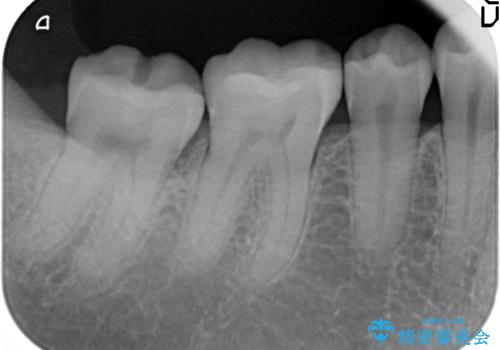

- 右下の銀歯を白くしたいといらっしゃった方の症例です。

銀歯を除去し、セラミックインレーによる修復を行いました。

当院のセラミックインレーはemaxという強度と審美性に優れた材料を使用しています。

またプレス方式でインレーを製作しているため、削り出しで製作するCADCAMより優れた適合性も持ち合わせており、虫歯が再発しにくい修復物です。